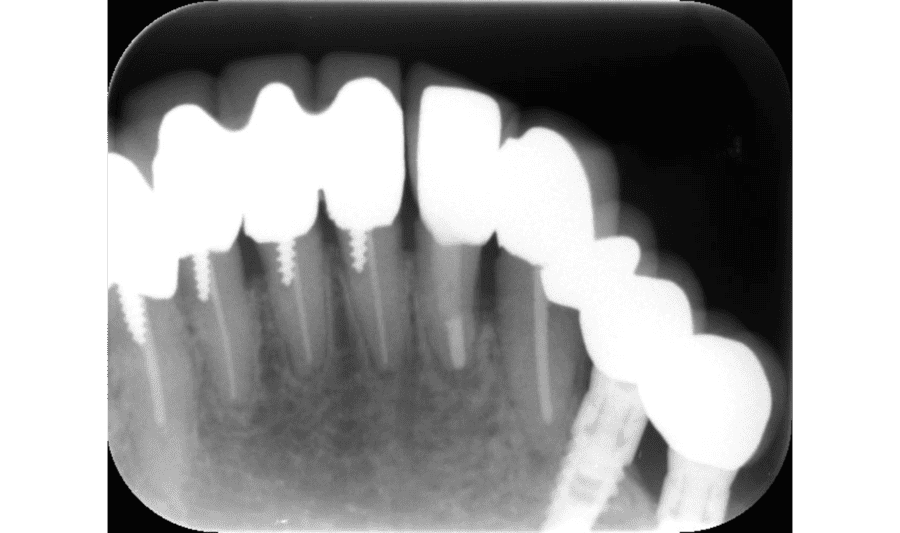

Before

術前(骨が大きく溶けた状態)